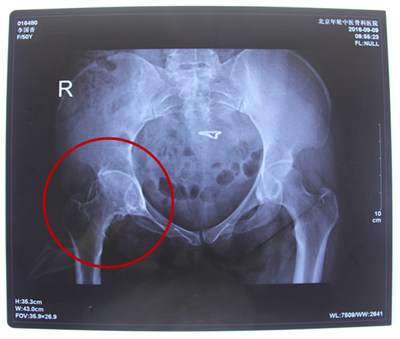

诊断结果:右侧股骨头缺血性坏死伴有右侧髋关节骨性关节炎

病情描述:患者于7年前因无明显诱因出现右髋腹股沟区及外上方疼痛,表现为隐痛,行走跛行。于久行及劳累后加重,就诊于当地医院,诊断为右侧股骨头缺血性坏死,给予口服中药一年,右侧髋关节疼痛症状有所缓解。2012年在北京航空医院行右髋关节介入治疗,术后右髋关节较之前疼痛减轻,但一段时间后疼痛加重。

2016年站立计划走进青海,在残联的帮助下患者顺利的加入站立计划项目当中来,由于家庭条件较为困难,经特殊批准得到站立计划的全额救助。来到北京年轮中医骨科医院接受治疗。经年轮股骨头医师会诊后决定对股骨头坏死病变区进行髋关节滑膜切除、清理并修正松解;同时取髂骨进行骨移植微创治疗,并辅以特制中医中药调理病况,由康复医师指导日常髋关节功能的恢复。